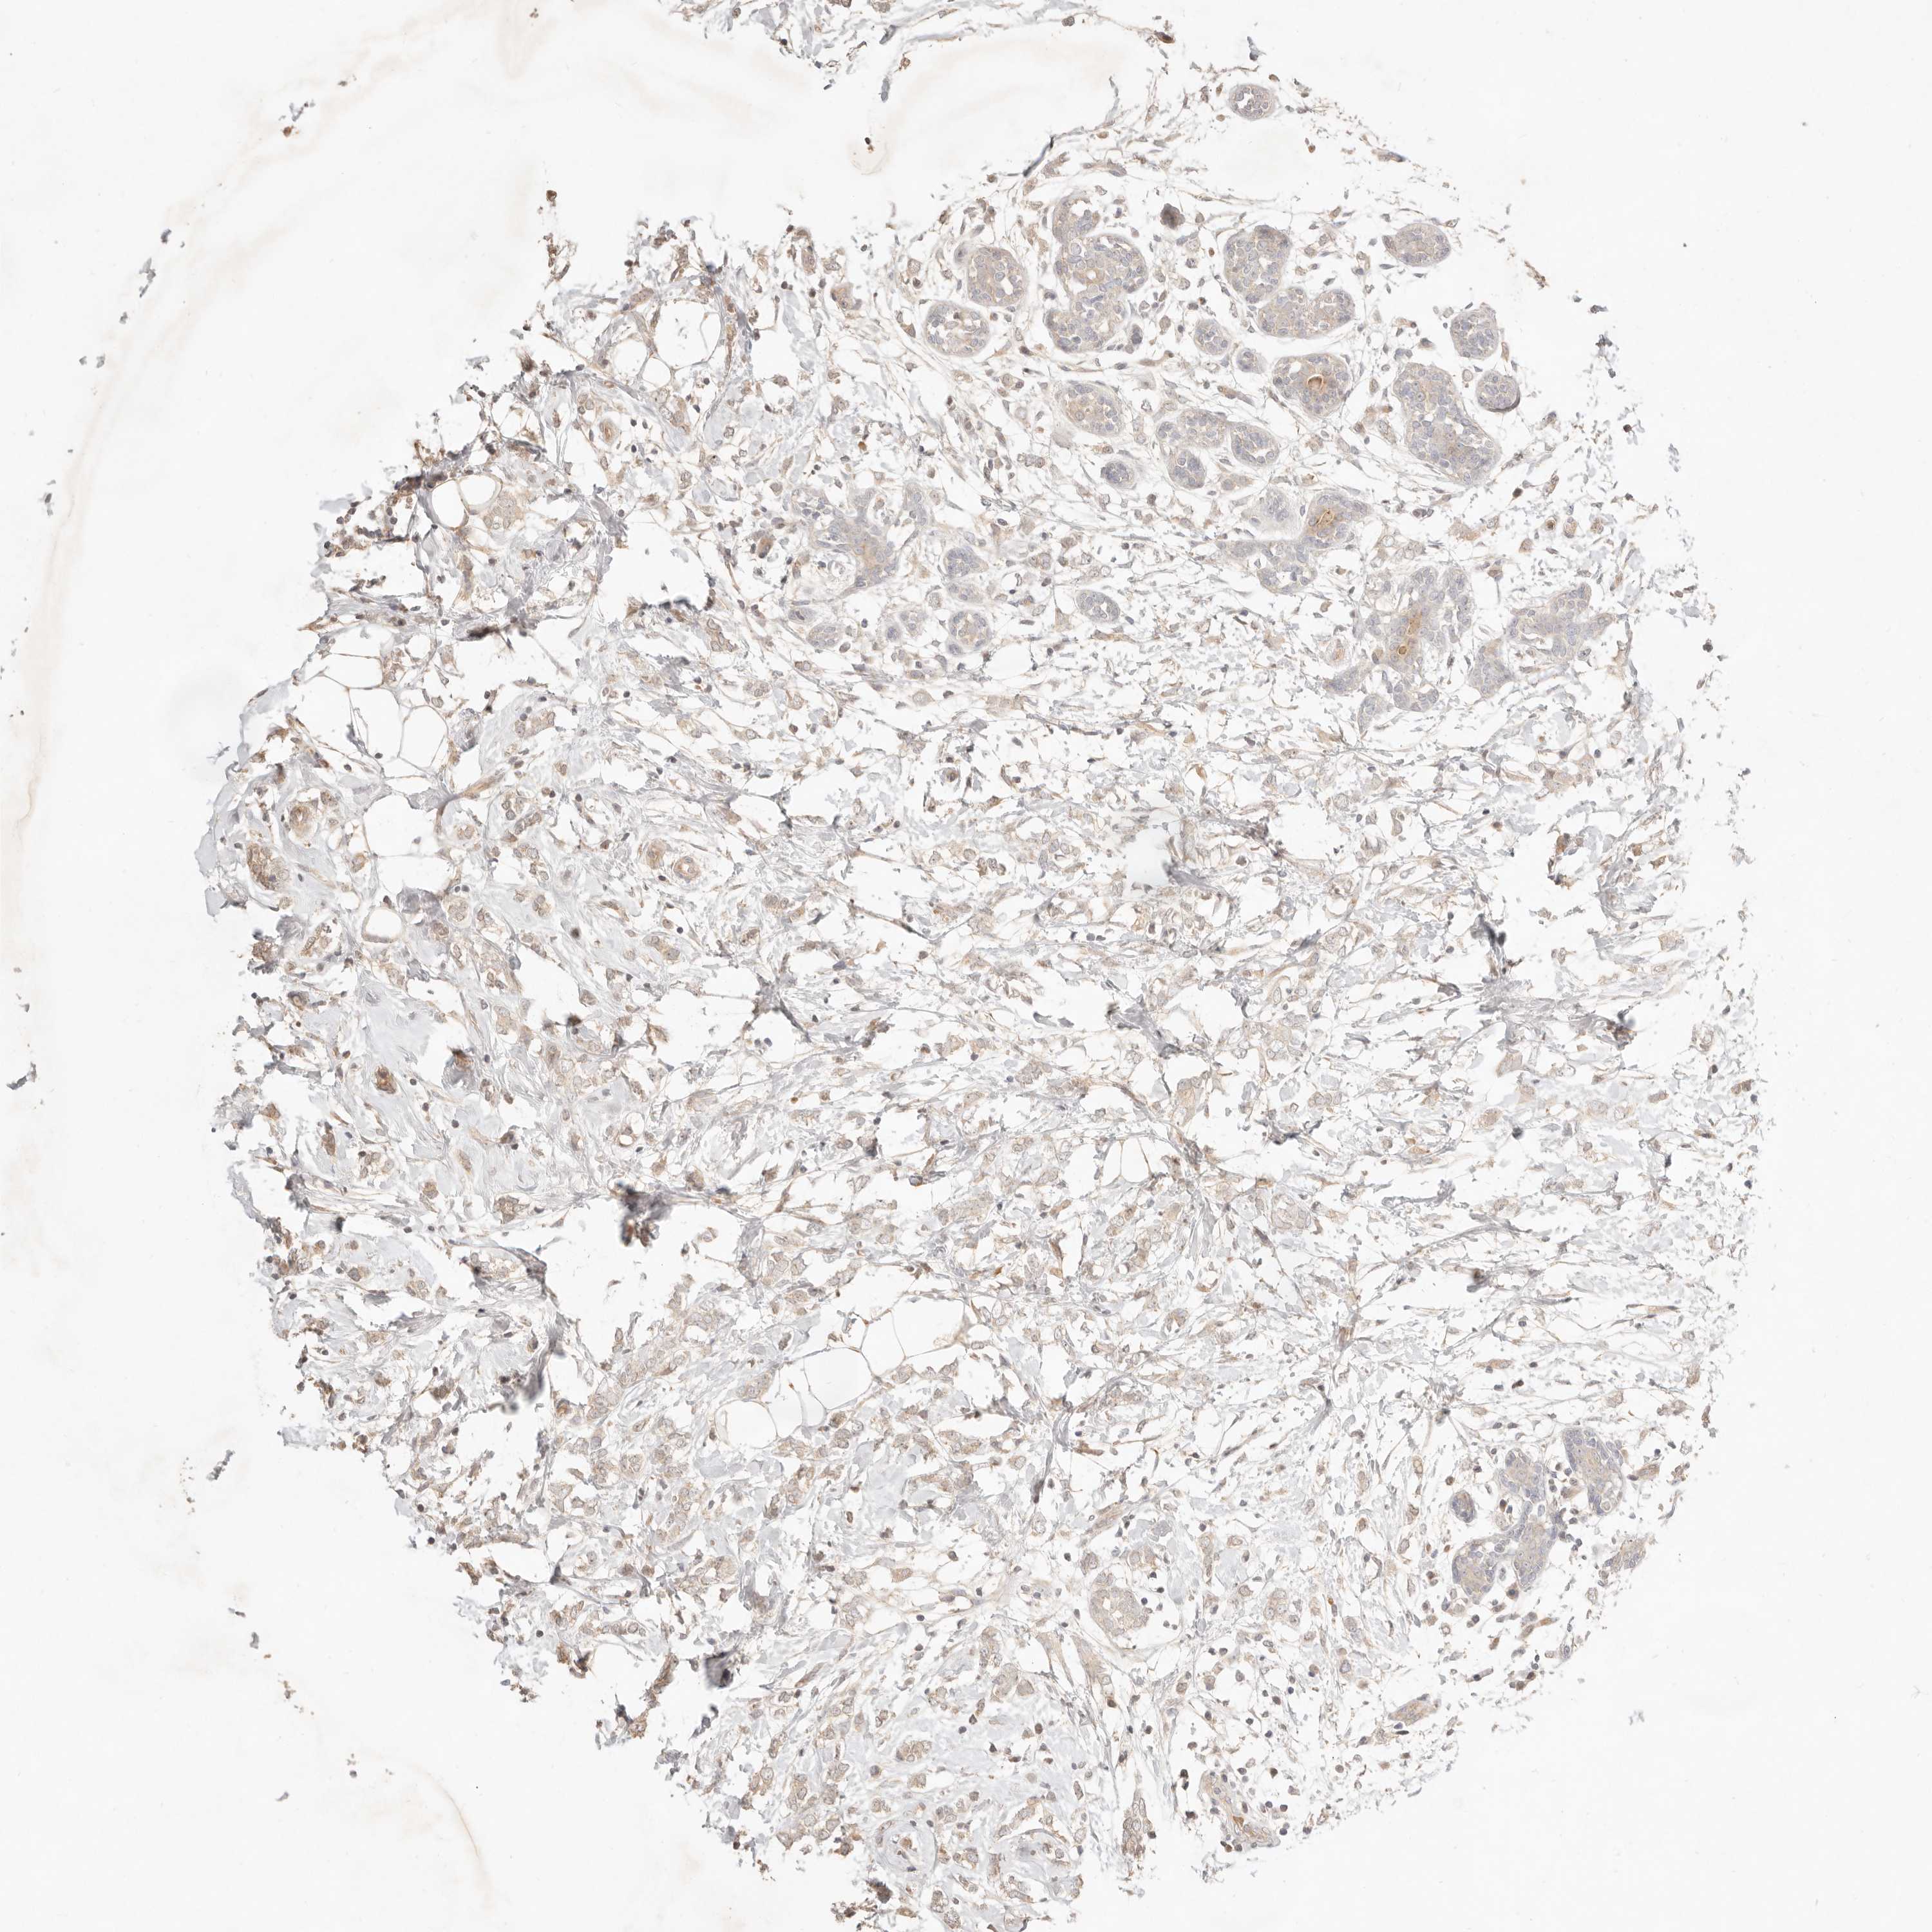

CANCER BREAST CANCER Show tissue menu

BRCA TCGA BRCA VALIDATION PROTEIN EXPRESSION